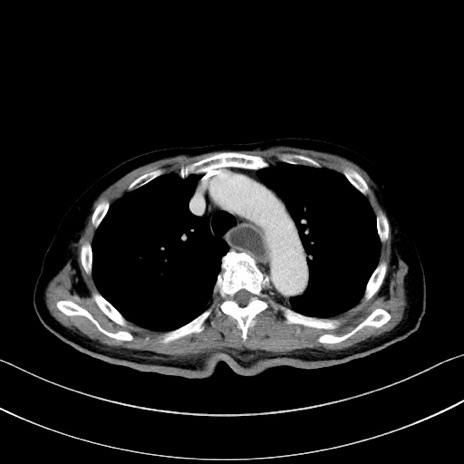

症例28(横断像)

【症例】60歳代男性

【主訴】嘔吐

【現病歴】胃癌にて胃全摘後。食思不振が悪化し、夜中に嘔吐することがある。

【既往歴】胃癌、胃全摘、脾摘、胆摘後

【データ】WBC 5900、CRP 10.56